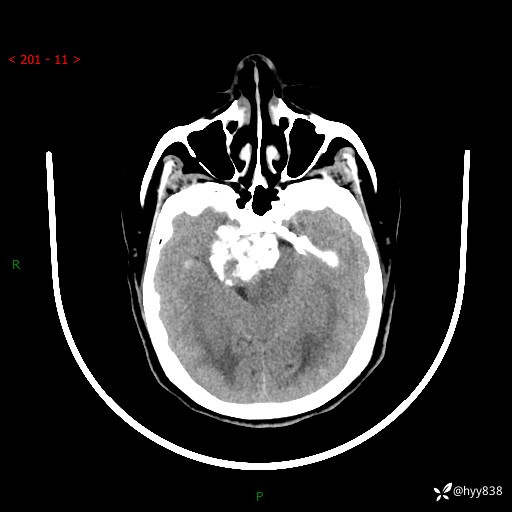

52岁/女,发现颅内占位4天。颅底钙化性肿块---结果公布~

颅脑CT平扫